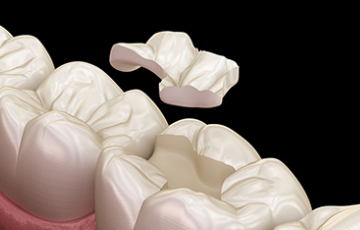

편리하고 빠른 디지털 치료가 가능합니다.

임플라인치과는 디지털 기술력과 원내 기공소를 구축 하였습니다.

베테랑 기공사 및 의료진 협업으로 빠른 치료가 가능합니다.

• 01

3D CT를 통한 정밀 진단

• 02

정밀한 진단 후 디지털 스캔

• 03

보철물 디자인

• 04

보철물 제작

• 05

보철물 부착

• 06

마무리 브리핑